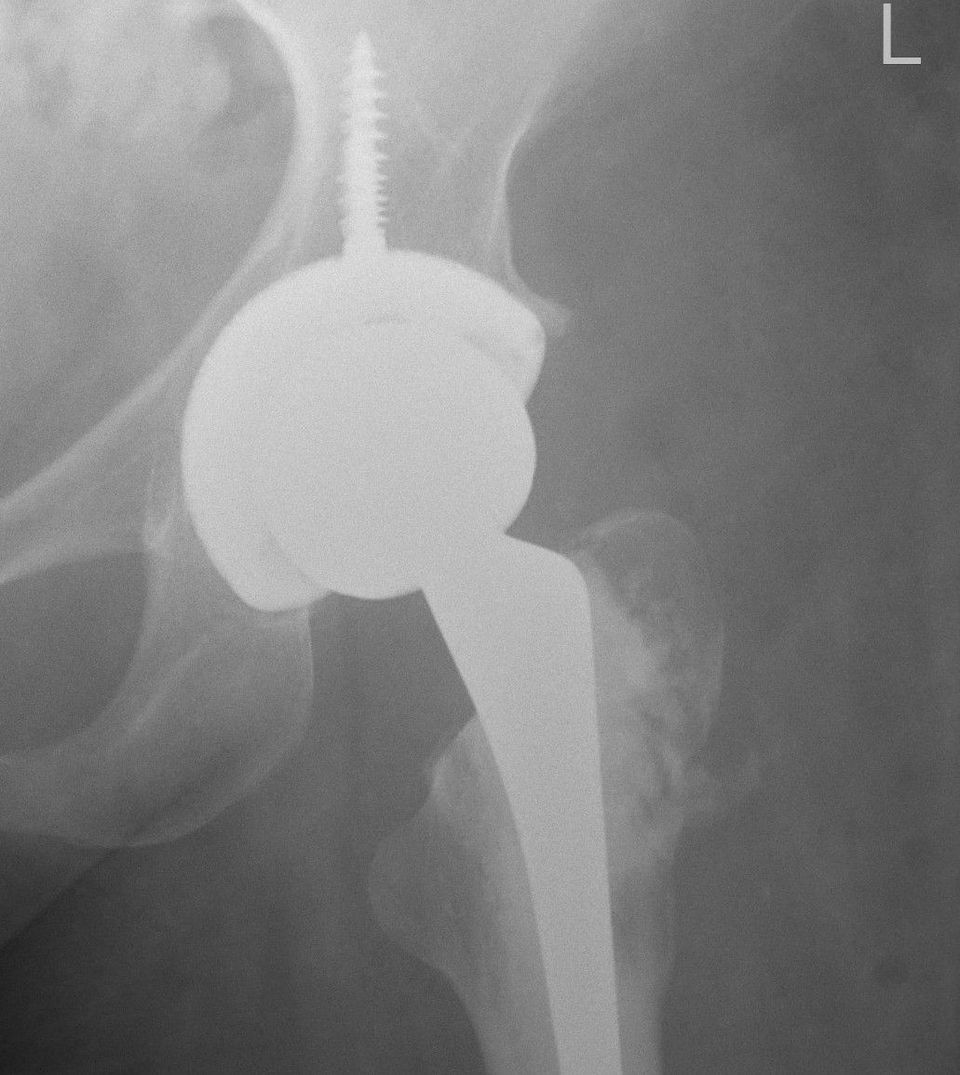

It turned out I needed another operation - I'm just back home from a hip replacement. The operation was successful, I was out of hospital in less than two weeks, and physical recovery is going well.

In April I went in for a routine scan to see how the hip was healing. It turned out the ball of the hip might be dissolving, and if it was it would need a hip replacement. I felt myself falling down a trapdoor of another extended hospital stay and another devastating setback in mobility. Just this time I would be starting off from a worse position.

He heard my concerns about rehabilitation and about how soon I would be able to put weight on the leg. He told me about how he would do the procedure and how he was taking those factors into account. He advised the physio team to see me in person before the operation so we could plan out what was needed for rehabilitation.